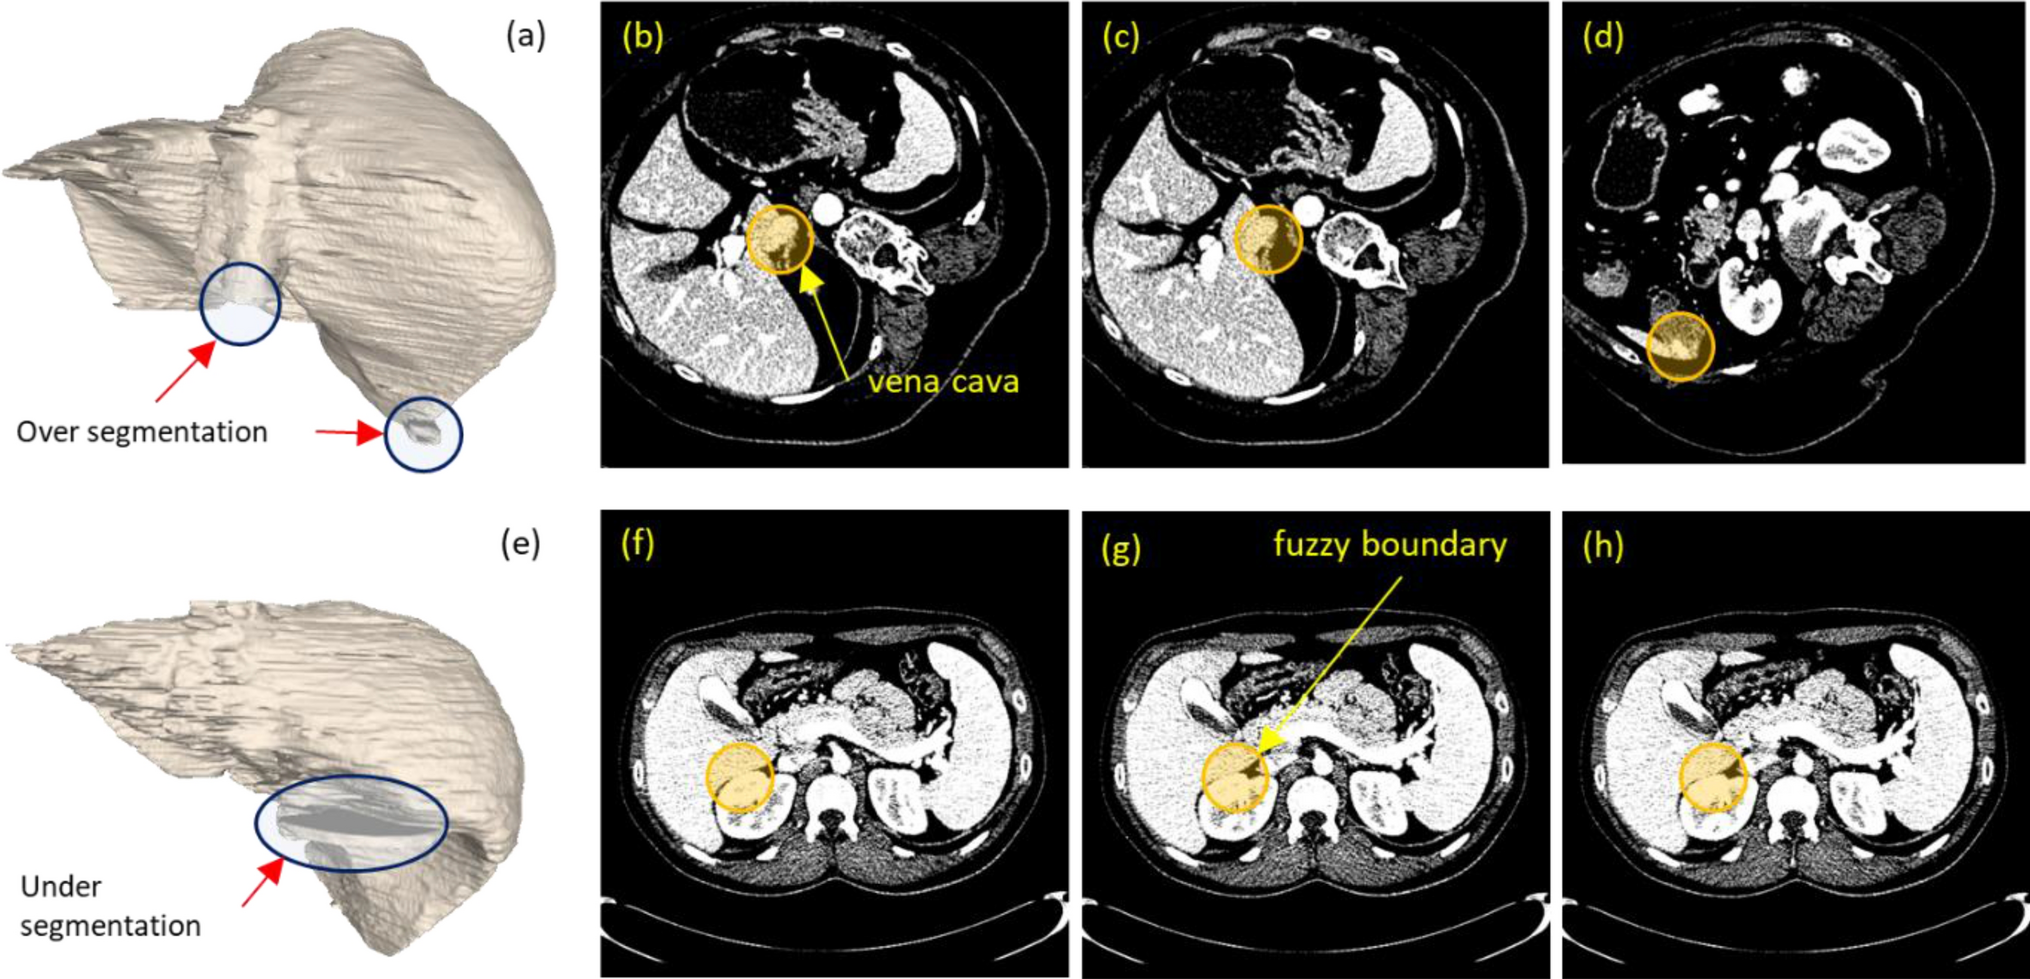

Figure 8

Examples of 3D segmentations (a) and (b), i.e., case 05 (top row) and 09 (bottom row), whose scores were the highest and the lowest, respectively. The corresponding images on their right shows CT slices where over (b), (c), and (d) and under (f), (g), and (h) segmentation occurred.